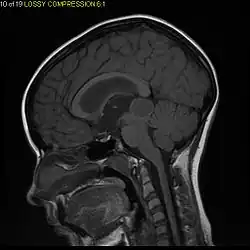

Usually – depending on the interview of the patient and after a clinical exam which includes a neurological exam and an ophthalmological exam – a CT scan and/or an MRI scan will be performed to confirm the presence of a tumor. They are usually easily distinguishable from normal brain structures using these imaging techniques. A special dye may be injected into a vein before these scans to provide contrast and make tumors easier to identify. Pilocytic astrocytomas are typically clearly visible on such scans, but it is often difficult to say based on imaging alone what type of tumor is present.

Pilocytic astrocytoma (and its variant pilomyxoid astrocytoma) is a brain tumor that occurs most commonly in children and young adults (in the first 20 years of life). They usually arise in the cerebellum, near the brainstem, in the hypothalamic region, or the optic chiasm, but they may occur in any area where astrocytes are present, including the cerebral hemispheres and the spinal cord. These tumors are usually slow growing and benign, corresponding to WHO malignancy grade 1.[1]